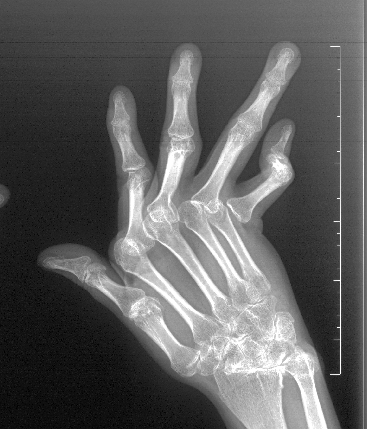

之后,李女士因间歇性停药导致病情反复,关节肿痛如影随形。更令人揪心的是,双手关节开始变形,掌指关节半脱位、手指向尺侧偏斜,原本灵活的指尖逐渐变成了“鹅颈样畸形”。严重的关节畸形让她不得不放弃工作,生活被无助与自卑层层包裹。

李女士的情况并非个例,作为一种累及全身小关节的致残性疾病,我国类风湿关节炎患病人数超500万,15年以上致残率高达 61.3%。与髋、膝关节等大关节置换不同,手指小关节置换堪称 “精细活”,尤其是类风湿关节炎患者,手术难度更是呈几何级增加。

患者可能同时存在 “纽扣样畸形”“鹅颈样畸形”“尺偏畸形” 等多种问题,成品假体无法匹配;